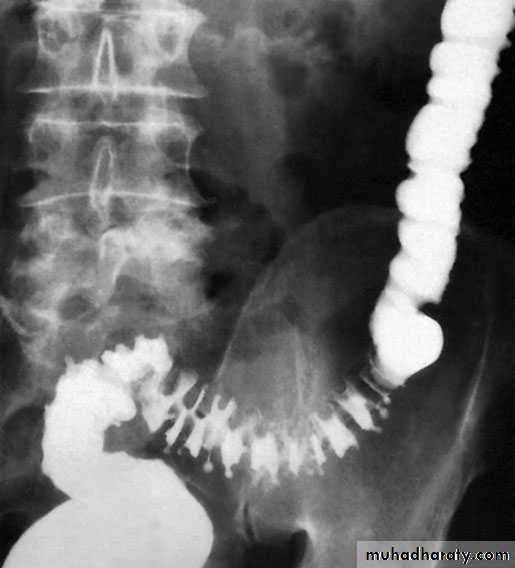

Barium enema showing sigmoid diverticular disease ‘saw-teeth’ and diverticula

Excessive segmentation in response to food, prostigmine and morphine is found in colonic motility studies, and this exaggerated response is more apparent in symptomatic than in asymptomatic individuals. On histological investigation, the diverticulum consists of a protrusion of mucous membranes covered with peritoneum. There is thickening of the circular muscle fibres of the intestine, which develops a con-certina or saw-tooth appearance on barium enema .

Water-soluble contrast enemas may, however, be helpful in sorting out patients with large bowel obstruction. Barium radiology is carried out to exclude a carcinoma and to assess the extent of the disease. Where the sigmoid colon is thickened and narrowed, a 'saw-tooth’ appearance may be seen.